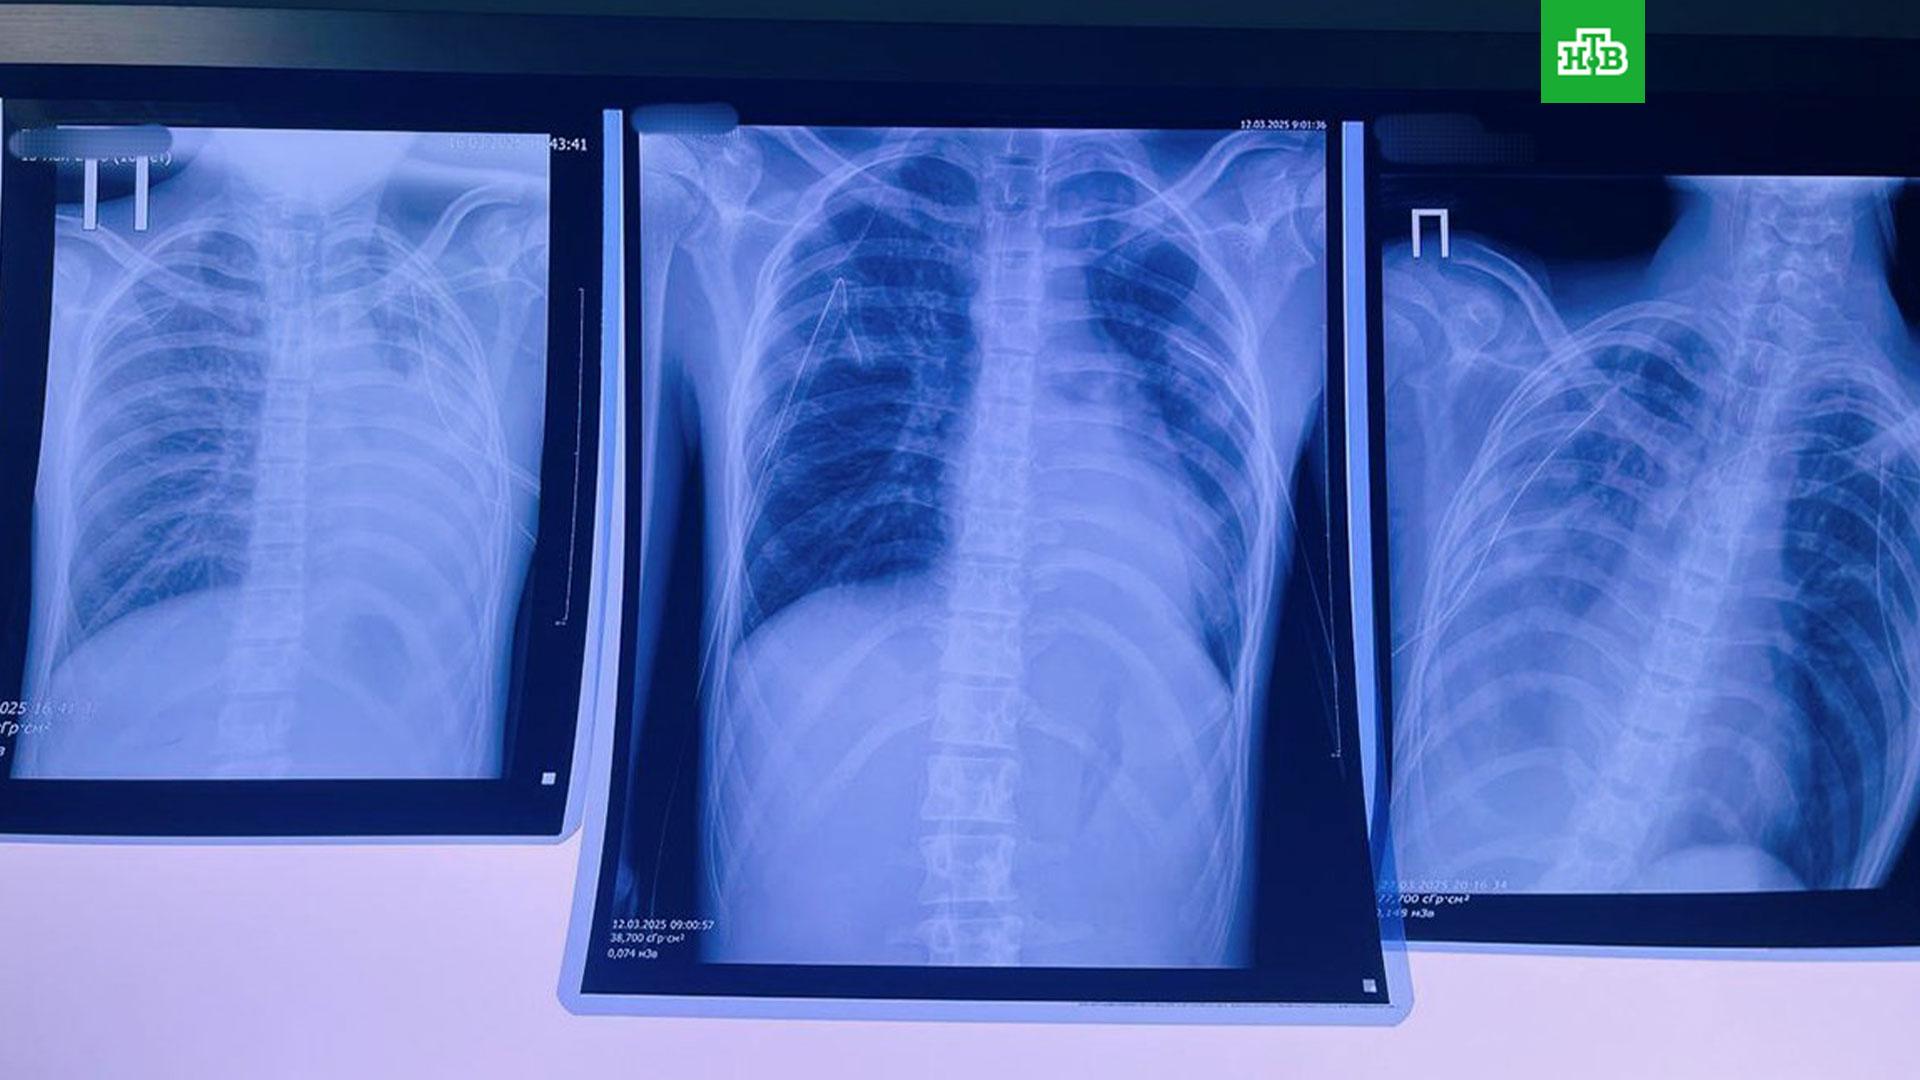

У девушки, которая четыре года курила сигареты и параллельно еще три года — вейп, выявлена двусторонняя полисегментарная бронхопневмония и обструкция бронхов. Жаловаться на кашель она стала еще осенью 2024 года, но с приступами удавалось справиться. Однако в начале

А у юноши, несколько лет подряд курившего вейпы, в легких за это время появились так называемые буллы — пузыри, которые образуются на тканях. В